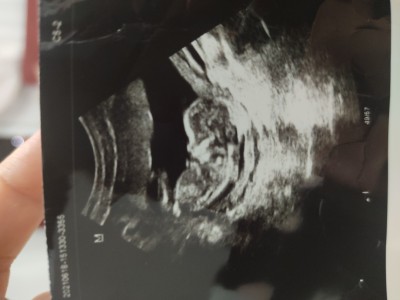

Tahmin alabilirmiyim

Sorum yukarda

cok minnos cikmis ^_^

Erkek diyroim doktor ne dedi cnm

Kız tahmin etti ama

Belli olmaz daha canm sağlıklı turp gibi olsun yeter gerisi

Çok yakışıklı canım

Kız tahmin etti canım:)

Bence bu minnos bir kiz

Erkek gibi

baby girl buu

Bayby boy

Ay bilemicem de yavrucak cok kakık yatıyor kıyamadım görünce